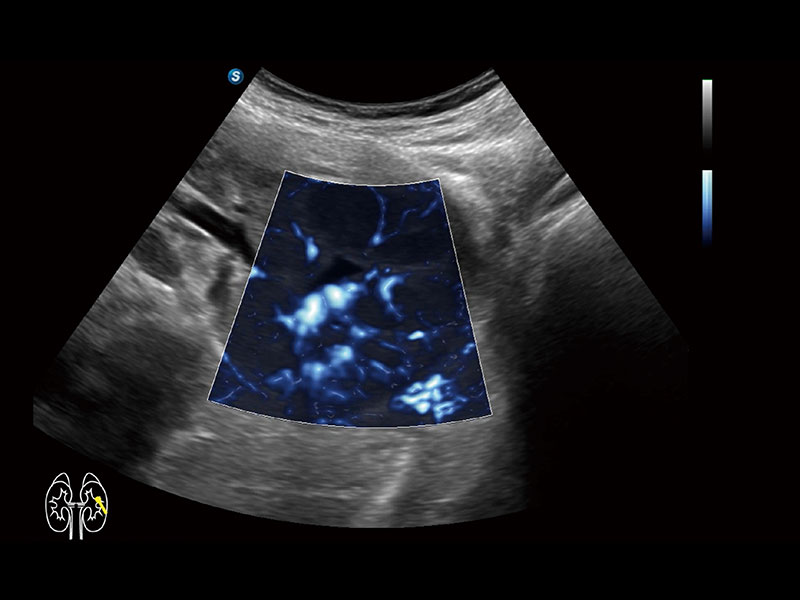

便携式彩色多普勒超声诊断系统

作为开立医疗全新打造的高端全域笔记本超声,X11集成了当前先进的硬件架构和精密的设计工艺,提升多科室临床医生在常规影像检查中的诊断能力,为临床提供全面的诊疗支持。